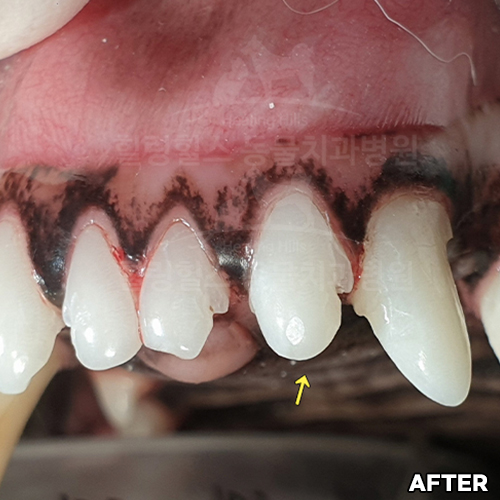

[깨진 강아지 치아 레진치료 전후]